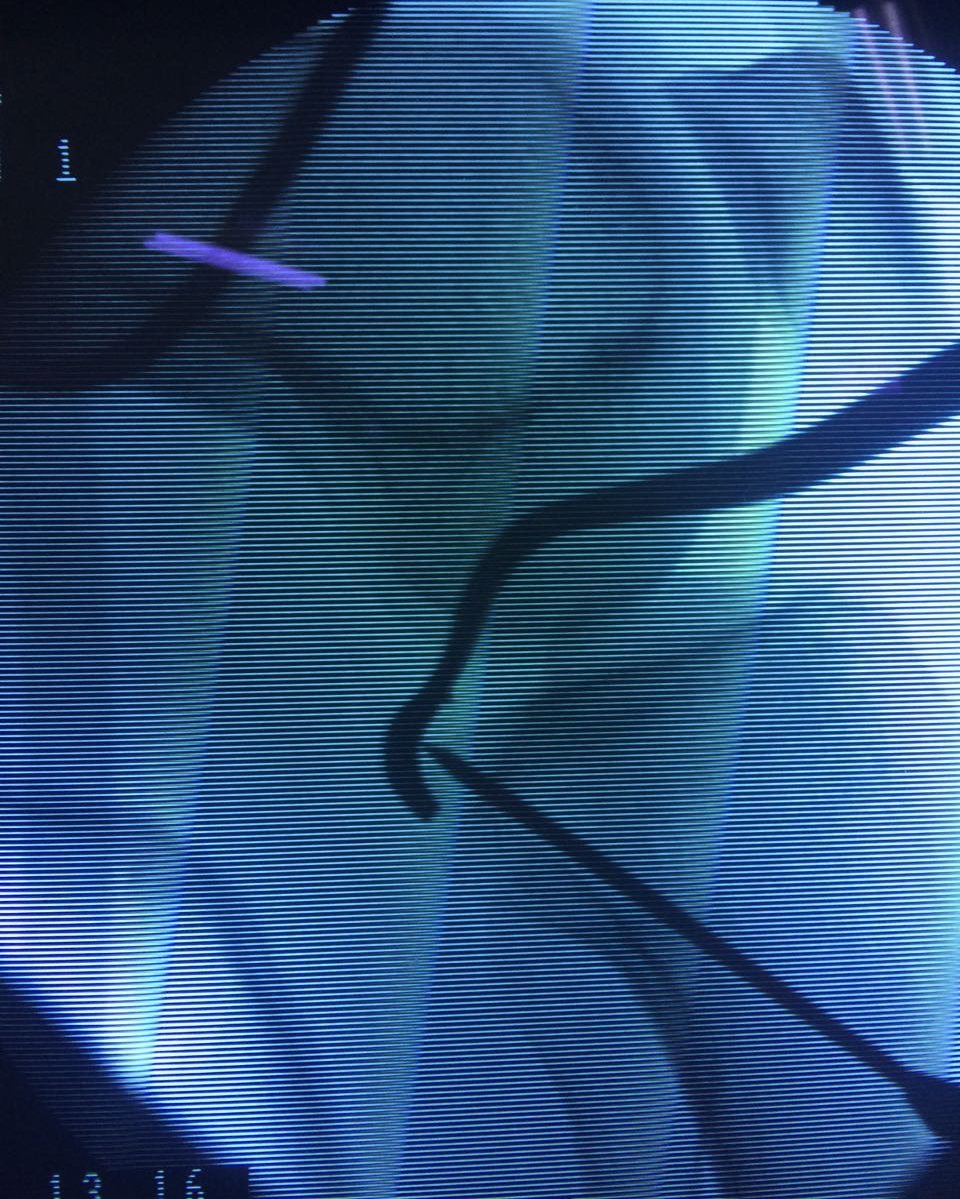

La artroscopia de rodilla es un cirugía en el cual la estructura interna de la articulación es examinada ya sea para realizar un diagnostico o para realizar un tratamiento, este procedimiento se realiza utilizando un instrumento parecido a un pequeño tubo llamado artroscopio.

La artroscopia se popularizo en 1960 y hoy en día es muy común en todo el mundo. Típicamente, es realizada por cirujanos ortopédicos de manera ambulatoria. Cuando se realiza de manera ambulatoria los pacientes pueden regresar a casa después de la operación, no se requiere quedarse en hospital.